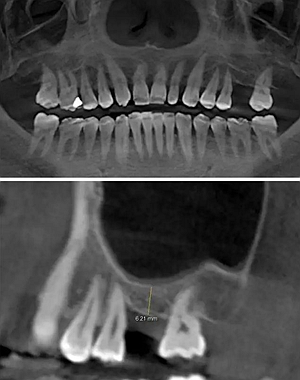

術(shù)前CBCT檢查

骨高度不足,內(nèi)提升的適應(yīng)癥??梢?jiàn)竇膜致密,厚度均勻。骨高度不足,骨寬度尚可。